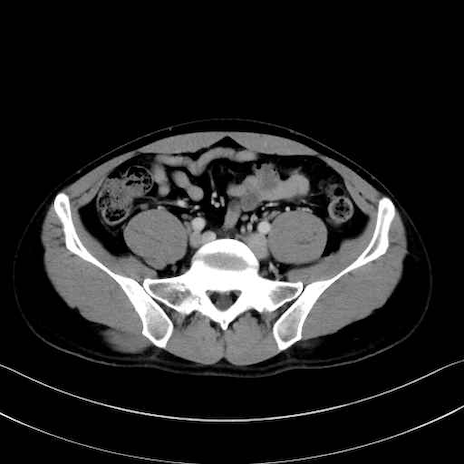

外閉鎖筋 (Obturator externus)